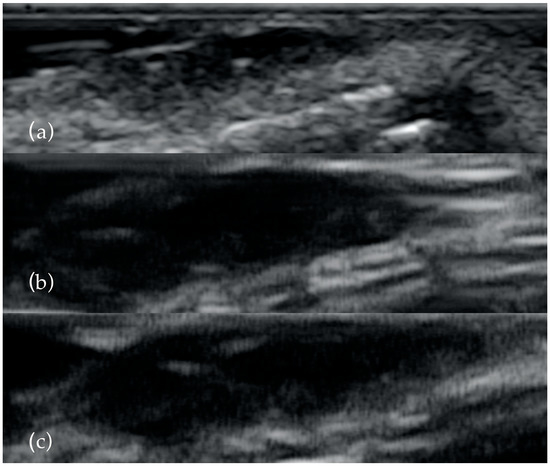

Figure 1.

The same BCC examined with 13 MHz (a), 20 MHz (b) and 40 MHz (c). As the frequency increases, the presence of the two hyperechoyc spots is clearer.